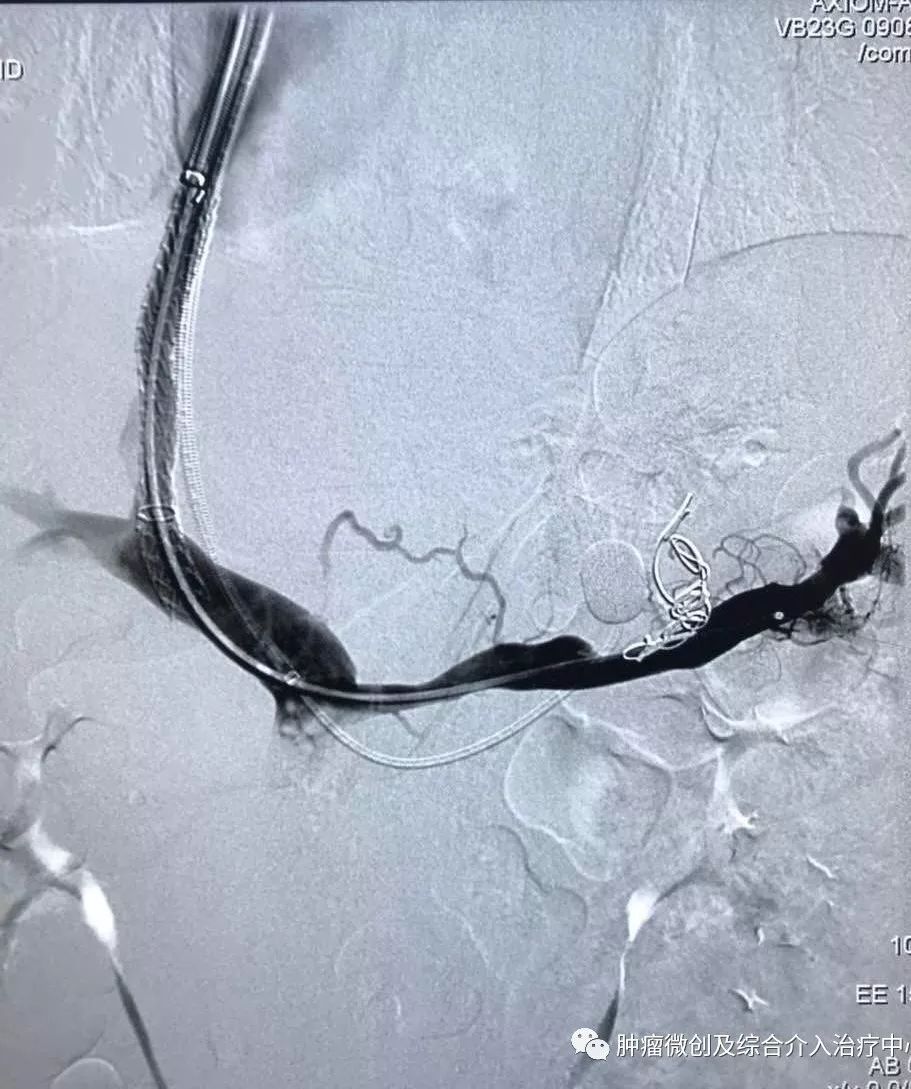

(肝静脉-门静脉穿刺成功,门脉高压,门静脉扩张明显)

(肝静脉-门静脉支架置入搭桥术,分流门脉部分血流,门脉压力降低)